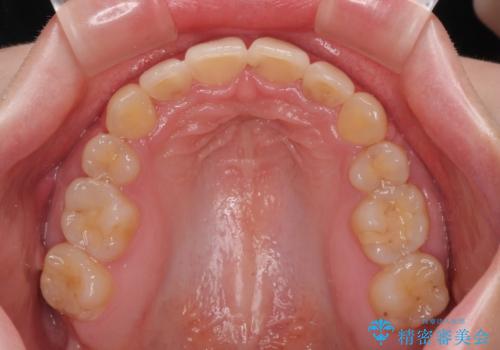

- デコボコになっている前歯を気にして来院された患者様です。

口元の突出感は気になっていないものの、デコボコを解消すると口元が前方に突出する可能性があるため、上下左右の第一小臼歯4本を抜歯して、ワイヤー装置にて矯正治療を行うこととしました。

下の前歯が隠れてしまうほど深く咬みこんでいたため、上顎前歯が前方に突出しているような印象がありましたが、咬み合わせが改善され、整った口元に仕上げることができました。